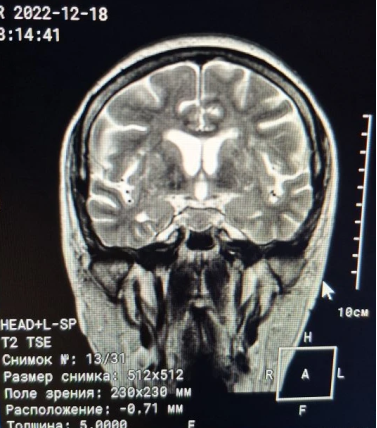

Затем, 17.12.2022, прошла МРТ головного мозга (рис. 4, рис. 5, рис. 6).

Рис. 4. МРТ головного мозга (T1 SE sag)

Рис. 5. МРТ головного мозга (T2 TSE)

Рис. 6. Заключение МРТ головного мозга от 17.12.2022